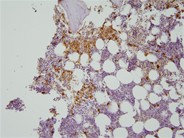

Bone marrow aspirate reveals normal mast cells when stained with May-Grünwald-Giemsa. These mast cells are characterized by their oval or irregular shape and possess a single central nucleus. The nucleus contains densely packed peripheral chromatin. The majority of the cytoplasm is occupied by cytoplasmic granules, which consist of small secretory granules ranging in size from 0.2 to 0.8 micrometers, as well as a few secondary lysosomes. Additionally, the cells exhibit small, finger-like projections extending from the cell membrane. In certain cells, the granules may be dense enough to obscure the visibility of the nucleus. While mast cells share similarities with basophils, their mononuclear morphology and monoclonal antibodies allow for their differentiation.